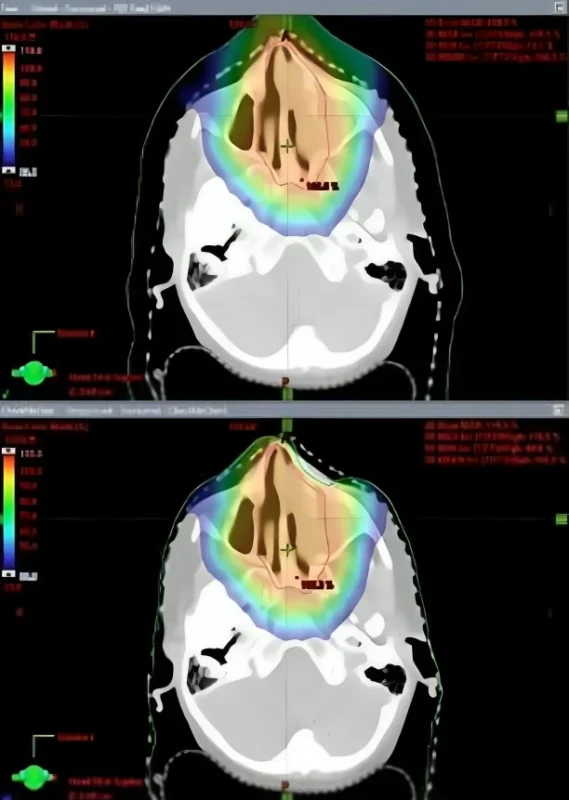

Figure 1: A) The dose distribution of the clinical plan with no error. B) Inappropriate “Body contour” edited intentionally leading to inaccurate proton range calculations.